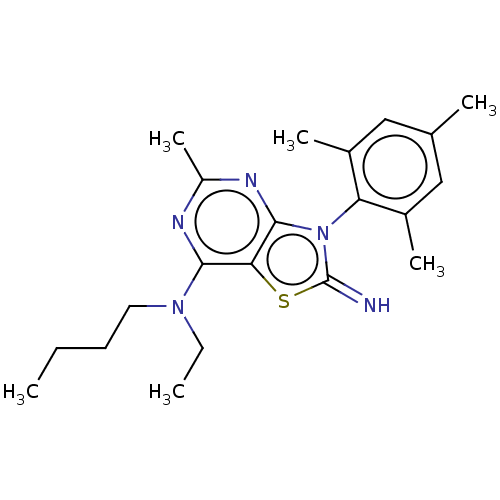

TargetCorticotropin-releasing factor receptor 1(Rattus norvegicus (rat))

Minase Research Institute

Curated by ChEMBL

Minase Research Institute

Curated by ChEMBL

Affinity DataEC50: 2.60nMAssay Description:Antagonist activity at rat CRF1 receptor expressed in CHO-K1 cells assessed as CRF-stimulated cAMP accumulation by enzyme immunoassayMore data for this Ligand-Target Pair